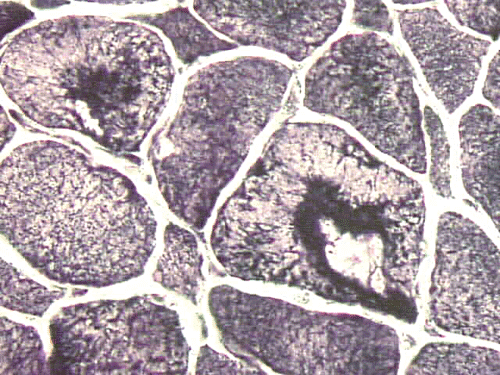

On hematoxylin-eosin stained sections, there is an increased variation of fiber diameter with many atrophic fibers intermingled with fibers of normal caliber. There is no evidence of fiber grouping or perifascicular atrophy. No inflammatory cells are present. There is also mild interstitial fibrosis (Panel A). On higher magnification, many fibers have a round concentric structure (Panel B). Irregular, centrally located depositions are also identified on modified Gomori's trichrome. The concentric nature, however, is not as obvious as in the hematoxin-eosin stained sections (Panel C). Type I and II fibers are not clearly separated in the ATPase preparation at pH 9.4. This is a common situation in chronically ill muscle (Panel D). The type I fibers are unusually dark. There is an increase in the proportion of type I fibers. The atrophic fibers are usually type II fibers. The concentric lesions are found predominantly in type I fibers (Panel E). There is an increase in PAS staining which is consistent with increased glycogen storage (Panel F). No increase in lipid content is demonstrated by oil red O (Panel G). On NADH-TR reaction, the concentric structures appear to have a clear central core that is devoid of enzymatic activity, a rim with intense enzymatic activity and a surround zone with relatively normal reactivity. These features are classic for target fibers (Panel H and I). No deficiency of laminin-2 (merosin) (Panel J) or dystrophin (Panel K) is demonstrated by immunohistochemistry. The central lesions are also immunoreactive for both laminin-2 and dystrophin. Immunohistochemistry for desmin demonstrate a core of strong immunoreactivity and also strong reaction in the sarcoplasmic membrane (Panel L and M). The target structures are also well demonstrated on semithin sections (Panel N). On electron microscopy, z-disc streaming is a common finding and they are often admixed with a substantial amount of dense granular electron dense substance (Panel O and P). There are also numerous cytoplasmic bodies characterized by radiating intermediate filaments (spheroid bodies) (Panel Q and R).